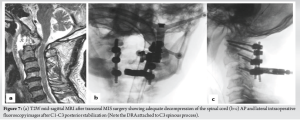

After 24 h of overnight intubation, staged posterior stabilization from C1-C3 was performed 7 days later. The patient was positioned prone on a Jackson table and the head was stabilized using a Mayfield head holder. Using a midline skin incision, C1–C3 was exposed bilaterally by exposing the C1–C2 joint and C1 lateral masses. For this, we exposed the venous plexus and cut the C2 nerve roots B/L. Bleeding from the vascular plexus was controlled using a combination of bipolar cautery, hemostatic matrix – Floseal; Baxter Healthcare Corporation Fremont, CA 94555, USA) and, gel foam. Using the navigation, it was noted that the pedicle on the right side of C2 was very narrow and precluded the placement of a pedicle screw, hence, a pars screw was preferred. A pilot hole was created with the aid of navigation, followed by insertion of the probes, taps, and screws according to the measured lengths. Finally, rods were inserted and C1–C3 stabilization was performed (Fig. 7). Bone grafts (allografts with demineralized bone matrix – Grafton DBM; Osteotech, Eatontown, New Jersey) were placed on the lateral gutters and no decompression was performed.

During both stages, there were no changes in the neuromonitoring signals. The patient was extubated and monitored in the high-dependency ward for 48 h and shifted to room air ventilation. His neurological examination showed improvement in motor strength to MRC grade 5/5 in all four limbs. Ambulation was initiated on the 2nd post-operative day under the guidance of a trained physiotherapist. The patient was maintained on a nasogastric tube for 2 weeks and then gradually advanced from liquids to soft regular foods. The biopsy report suggested the lesion as a synovial cyst. Regular follow-up was performed at 1, 3, 6, and 12 months postoperatively. At our last follow-up of 3 years, clinical and radiological results were satisfactory (there was complete recovery of motor power in all four limbs, and was able to ambulate independently. Radiologically, there were no signs of C1-C2 instability and implants were in place without any evidence of screw loosening, pullout, or rod breakage).